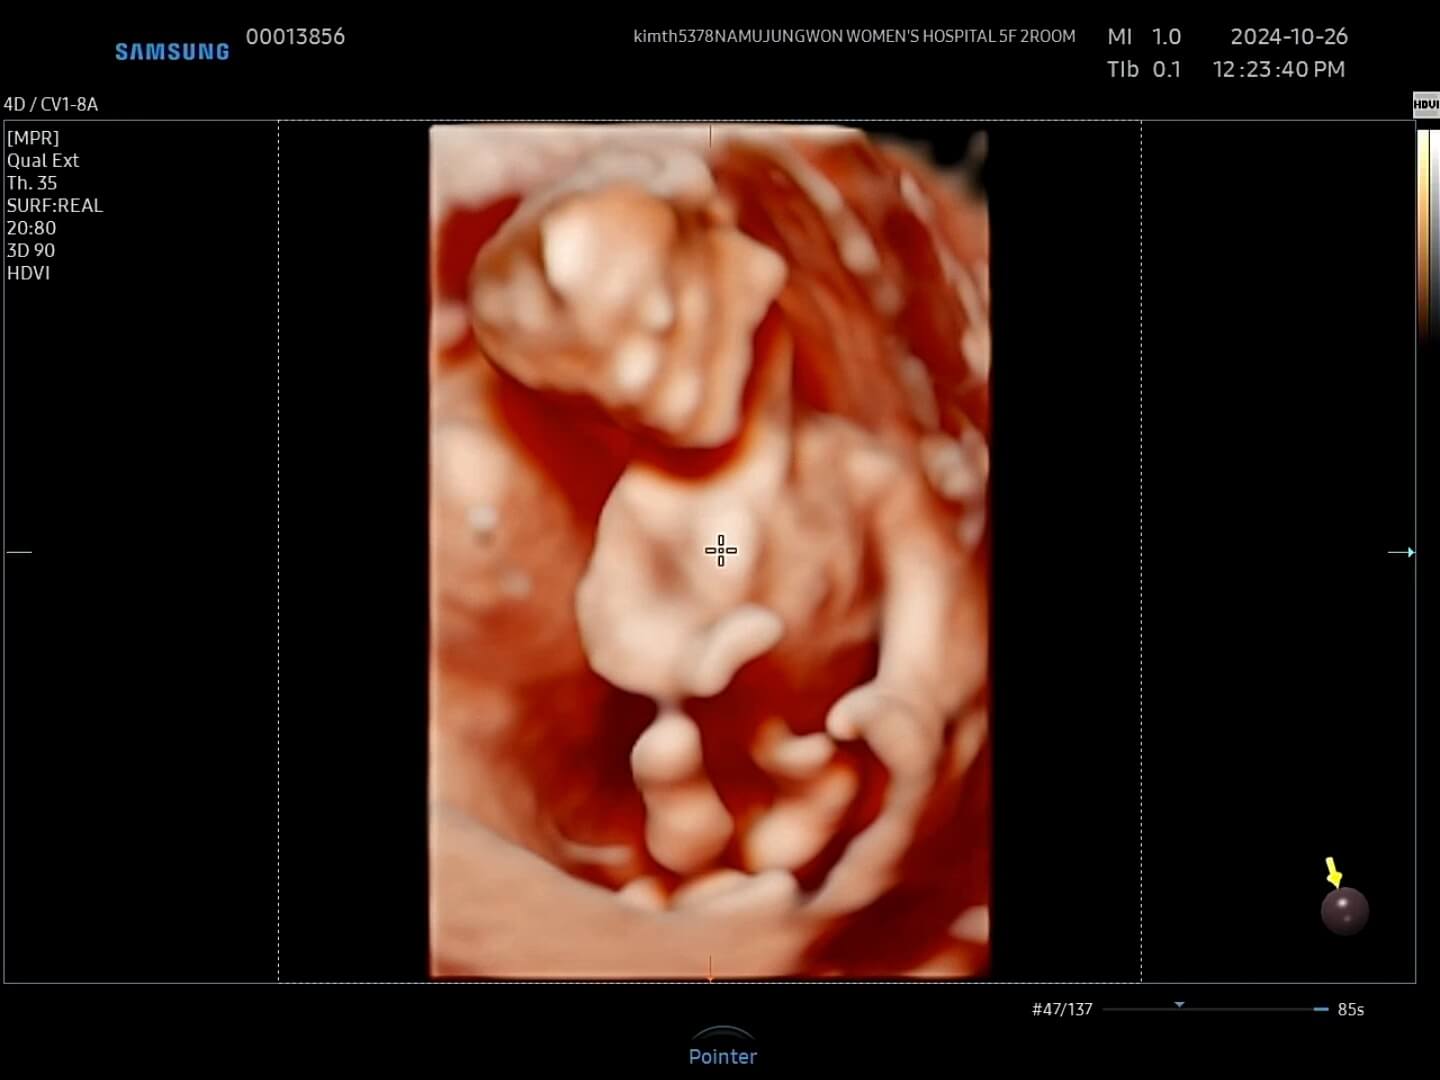

4. 12주 입체초음파

드디어 12주가 되어 꾸미의 첫 입체초음파를 보는 날이 되었어요! 두근두근, 꾸미는 얼마나 커있을까요?

12주-입체초음파 12주에는 첫 입체초음파를 보게 되면서 팔, 다리가 잘 형성되었는지 정도를 보는 것 같아요. 12주부터 '태아'라고 부르기도 한답니다. 우리 꾸미는 처음에는 등을 돌리고 있다가 서서히 얼굴을 보여줬습니다. 벌써부터 귀여워요! 아들인지 딸인지 너무 궁금했는데요, 성별은 입체 초음파가 아닌 일반 초음파로 봐야한다고 하셨어요.